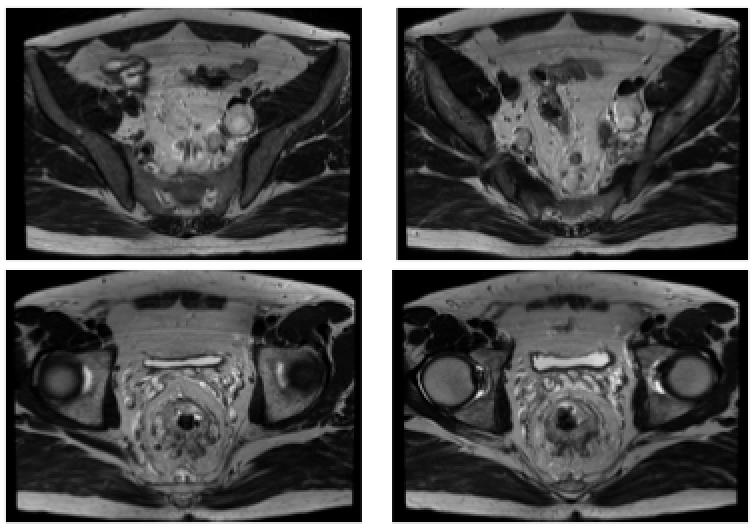

直肠MRI

DIS:直肠肿瘤位于:中下段,位于腹膜反折上、下,肿瘤下极距肛下缘约4.8cm。

T:肿瘤中心位于直肠后壁;侵及肠壁(突出浆膜、外膜);直肠系膜受累及(侵出肠壁约1.9cm),距离直肠系膜环周0.5cm。

A(肛管):肿瘤未累及侵犯肛管。

N(淋巴结):直肠系膜区及盆腔多发增大淋巴结,DWI呈高信号,T2WI呈高信号,最大位于左侧髂血管旁,直径约2.7cm。

C(CRM,环周切缘):增大淋巴结距离直肠系膜周边最近距离<1mm,系膜环周筋膜受累。

E(EMVI,壁外血管侵犯):直肠周围静脉丛可疑受侵犯

直肠中下段癌,距肛下缘4.8cm,位于腹膜反折上、下,肛管未受累,直肠系膜区及盆腔多发肿大淋巴结,环周切缘阳性,壁外血管可疑受侵犯。

DIS:直肠肿瘤位于:中下段,位于腹膜反折上、下,肿瘤下极距肛下缘约4.5cm。

N(淋巴结):直肠系膜区及盆腔多发增大淋巴结,DWI呈高信号,T2WI呈高信号,最大位于左侧髂血管旁,直径约4.0cm。

E(EMVI,壁外血管侵犯):直肠周围静脉丛可疑受侵犯。

直肠中下段癌,距肛下缘4.5cm,位于腹膜反折上、下,肛管未受累,直肠系膜区及盆腔多发肿大淋巴结,环周切缘阳性,壁外血管可疑受侵犯。

肝右叶小囊肿。

双肾多个小囊肿。

DWI